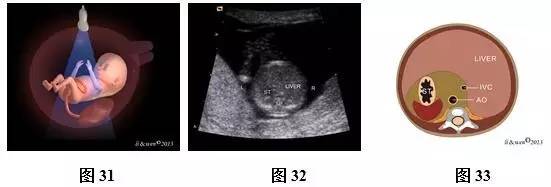

(三)11~13+6孕周胎儿腹部扫查方法及观察内容

超声扫查方法:声束通过胎儿上腹部的胃泡、肝脏横断扫查(图31),可获得上腹部横切面图(图32,33),然后声束平面向胎儿尾侧平移扫查,通过脐带腹壁插入口时(图34),可获得脐带腹壁插入口横切面(图35,36)。通过膀胱时(图37),可即获得膀胱水平横切面(图38,39)。

标准切面判断标准:腹部呈圆或椭圆形,脊柱为横切面,上腹部横切面可见正常胃泡位于左侧,肝脏位于右侧;脐带腹壁插入口横切面可见脐带腹壁入口位于前腹壁中央,与后腹壁脊柱回声连成一直线构成此平面的前后中轴线;膀胱水平横切面彩色多普勒可见膀胱位于盆腔内,呈无回声,在膀胱的两侧各有1根脐动脉,略向脐孔处旋转探头,可见脐血管在腹正中处进入脐带内。

主要观察的内容:(1)上腹部横切面:主要观察内容是胃泡及肝脏位置、大小。正常胃泡位于腹腔左侧,肝脏位于腹腔右侧。(2)脐带腹壁插入口横切面:腹壁完整性与连续性,脐带腹壁入口处位置是否正常、有无包或肠管外翻等。(3)膀胱水平横切面彩色多普勒:观察脐动脉数目,膀胱位置、大小及壁的厚度等。

注:ST为胃泡;LIVER为肝脏;SP为脊柱;IVC为下腔静脉;AO为腹主动脉;UA为脐动脉;L为左侧;R为右侧;

图31~39 11~13+6孕周胎儿腹部扫查方法、声像图及模式图。图31上腹部横切面图扫查模式图;图32、33上腹部横切面图声像图及模式图;图34脐带腹壁插入口横切面扫查模式图;图35、36脐带腹壁插入口横切面声像图及模式图(黑色箭头示脐带腹壁入口);图37膀胱水平横切面扫查模式图;图38、39膀胱水平横切面彩色多普勒。